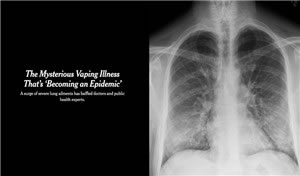

央视:美国2007年开始卖电子烟,为何"电子烟疾病"去年暴发

近日,美国国内和国际上出现越来越多的质疑声,要求美政府公布关闭德特里克堡生物基地的真实原因,查清德特里克堡生物基地关闭与“电子烟疾病”、大流感和新冠肺炎之间的关系。根据美国审计署早在2009年的一份报告,过去10年中,美国P3实验室发生了400起事故。生物实验室安全性问题是美国监管机构面临的最大风险。“电子烟疾病”和德特里克堡生物基地关闭、大流感和新冠肺炎之间的关系,还需要美国给公众一个交代。